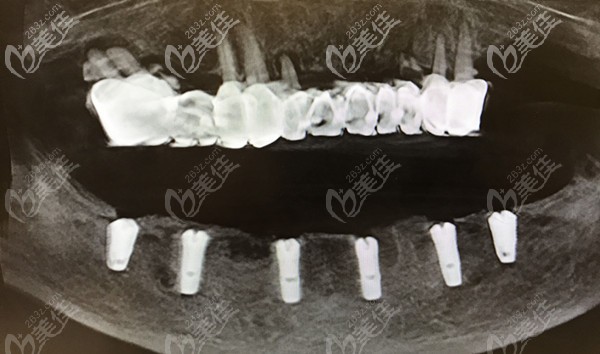

杭州美萊口腔成立于2014年,位于杭州市西湖區(qū)莫干山路,地理位置優(yōu)越,交通便利,是由杭州市西湖區(qū)衛(wèi)生健康局審批成立的醫(yī)療機(jī)構(gòu),深受愛美人士的信賴。開設(shè)項目:院內(nèi)設(shè)有牙齒矯正、正畸、牙齒修復(fù)、牙齒美白及綜合治療等項目,不管是從院內(nèi)環(huán)境,服務(wù)態(tài)度、就診體驗度還是消毒標(biāo)準(zhǔn)都為顧客安排的明明白白,也因此成為廣大顧客喜愛的口腔美容機(jī)構(gòu)。特色項目:ALL-ON-4微創(chuàng)即刻種植:只需種入4顆種植體,就可以恢復(fù)半詳細(xì)>